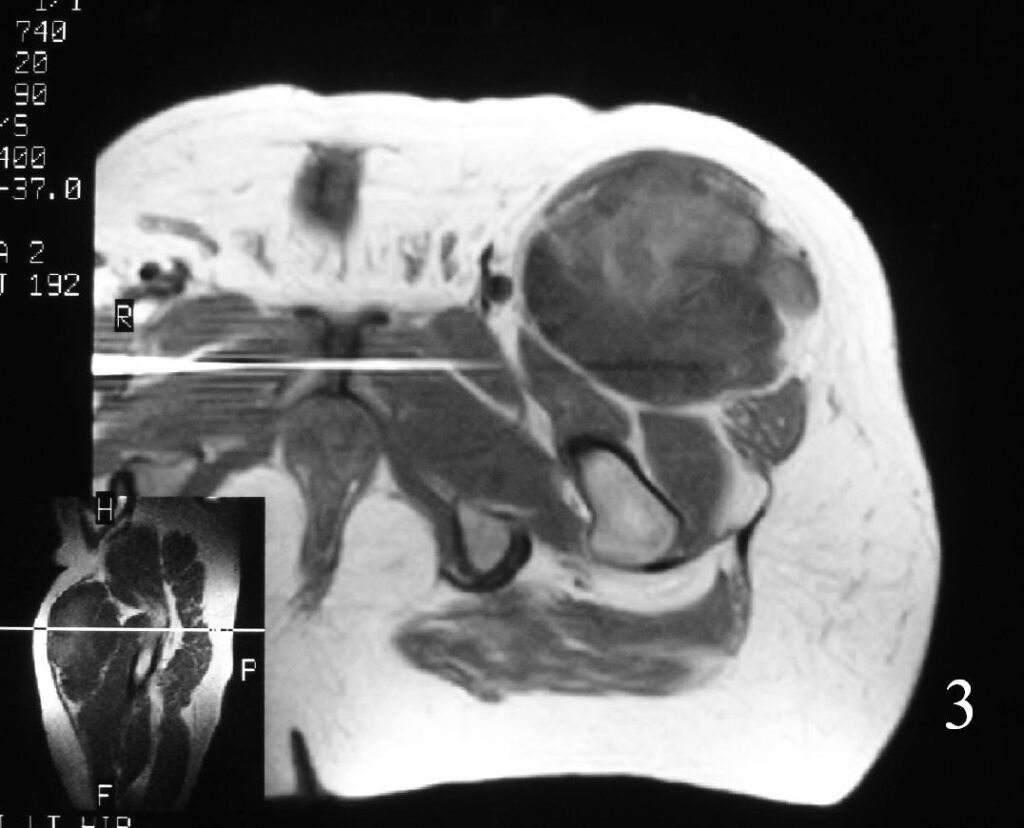

MRI (Fig. 3-7)

• Shows lobulated soft tissue mass

• Signal intensity similar to that of skeletal muscle on T1W

• Heterogenous signal intensity greater than that of fat on T2W

Fig. 3

Fig. 4

Fig. 5

Fig. 6

Fig. 7

Fig. 3-7 Axial MRI of the lower extremity shows an extraskeletal soft tissue chondrosarcoma in different sequences with and without contrast (Fig. 3, 4, 5). Sagittal MRI (Fig. 6, 7) T1 with-without contrast demonstrates enhancement of the mass